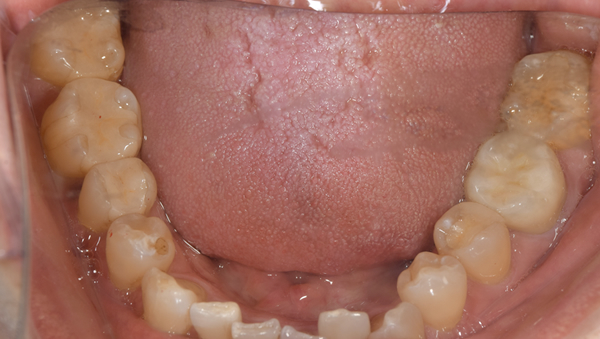

治療前:下の歯

担当医師所見:

下顎右側臼歯部には一見大きな問題はないように見えるが、 頰側にフィステルと言われる排膿路があり発赤と主張があり炎症状態が続いていた。